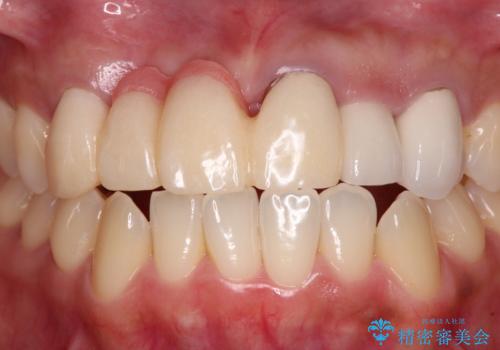

歯肉が痩せてしまっている状態を改善するため、口蓋から歯肉の結合組織を採取し、移植することで厚みを増大させることとし、その後オールセラミックブリッジにて補綴治療を行うこととしました。

1回の歯肉移植により歯肉の厚みは大幅に改善されましたが、折角なのでもう少し大きくしたいとの要望があり、2回目の処置も行うこととしました。

厚みも高さも十分な歯肉量を獲得することができました。